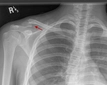

Doku zedelenmesi, yaralanma veya travma sonucu vücut dokularında meydana gelen hasarlardır. Bu durum, çeşitli doku türlerinde farklı belirtilerle kendini gösterir. Tedavi yöntemleri zedelenmenin türüne göre değişiklik gösterirken, önleme yöntemleri de yaralanma riskini azaltmaya yöneliktir.

Doku zedelenmesi, bir yaralanma veya travma sonucunda vücut dokularının hasar görmesi durumudur. Bu tür zedelenmeler, cilt, kas, sinirler ve iç organlar dahil olmak üzere çeşitli dokularda meydana gelebilir. Doku zedelenmeleri, genellikle ağrı, şişlik ve fonksiyon kaybı gibi belirtilerle kendini gösterir. Bu makalede, doku zedelenmesinin belirtileri, türleri ve tedavi yöntemleri üzerinde durulacaktır. Doku Zedelenmesi TürleriDoku zedelenmeleri, genel olarak üç ana kategoriye ayrılabilir:

BelirtilerDoku zedelenmesinin belirtileri, zedelenmenin türüne ve ciddiyetine bağlı olarak değişiklik göstermektedir. Yaygın belirtiler şunlardır: